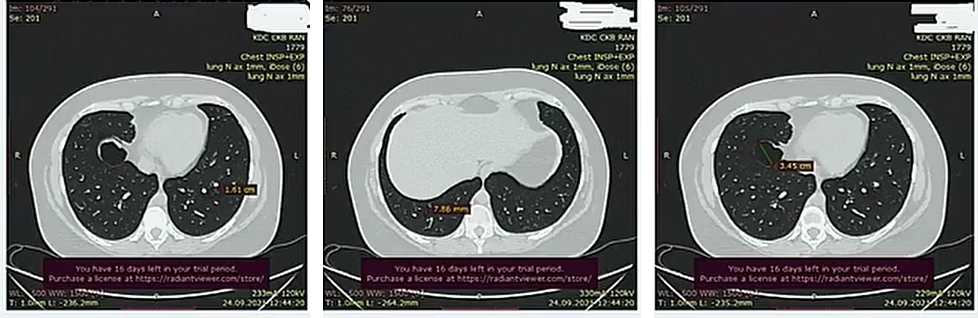

Данные инструментальных методов, КТ. Источник: личный архив доктора Ивахненко Е.Ф.